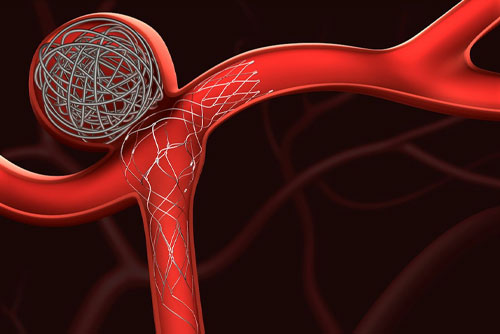

Aneurysm Coiling